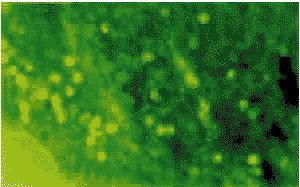

图1 癌间质中IgG产生细胞的表达

38例p53表达阳性的病例中,只有15例IgG表达(39.47%),而p53阴性的42例中,IgG阳性表达的高达30例(71.43%),两者之间有显著性差异(P<0.05)。同样,PCNA阳性的病例中,IgG阳性表达的只占39.02%,而PCNA阴性的病例中,IgG阳性表达的细胞高达74.30%(图1,2,3)(表2)。

, 百拇医药 1.3.1 免疫荧光染色法二甲苯脱蜡,无水乙醇及95%乙醇脱水,PBS冲洗加入FITC标记的羊抗人IgG马抗人IgM、IgA湿盒37℃孵育一小时,PBS冲洗,磷酸甘油封片,荧光显微镜下观察结果,细胞轮廓清晰,呈亮绿色荧光的细胞为抗体产生阳性细胞。